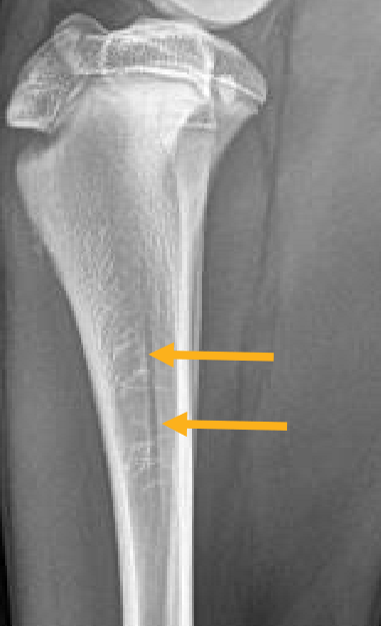

Location of the nutrient foramen

In the cortex of the proximal diaphysis in long bones

<p>In the cortex of the proximal diaphysis in long bones</p>